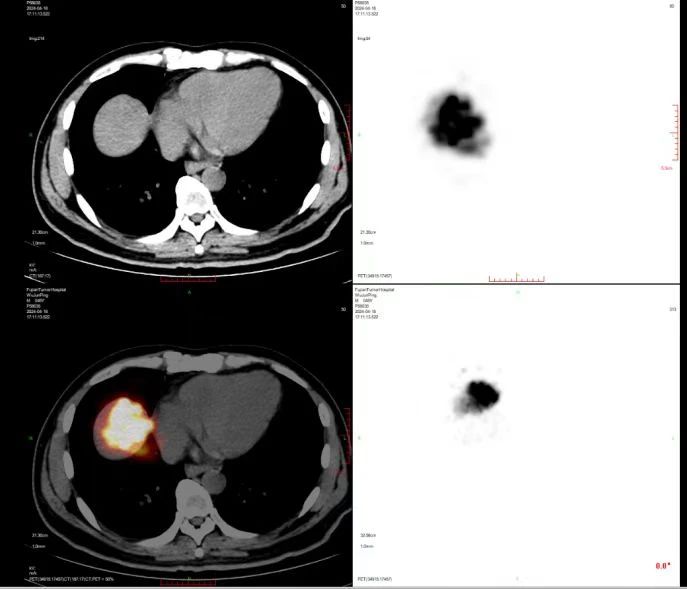

术后即时PET-CT显示钇90放射性微球完全分布在肿瘤内,正常肝实质未受影响

方主亭副院长介绍,肝癌起病隐匿,我国多数肝癌患者在初诊时就已进入中晚期,错失手术切除的机会。钇90放射性微球介入治疗适用于无法手术切除肝癌的患者。钇90放射性微球通过肝肿瘤供血动脉精准注入到肿瘤组织内部,发射高能量β射线杀伤癌细胞,具有高效缩瘤、安全性高的优点。